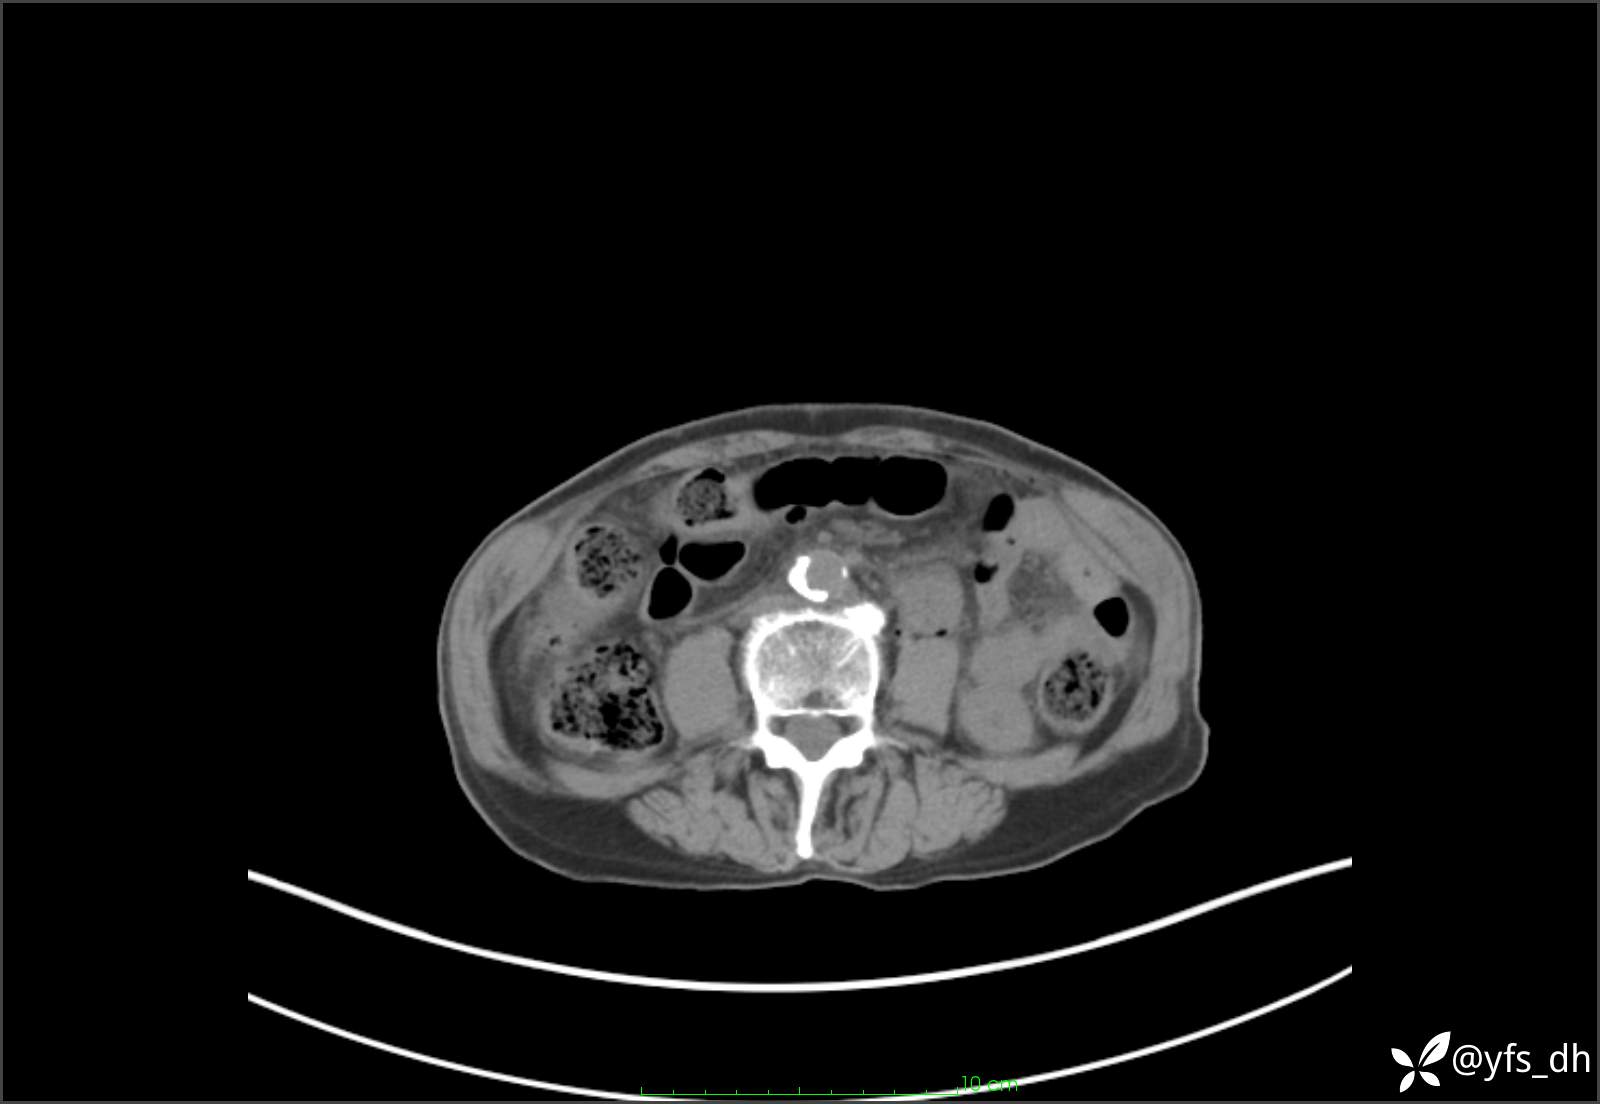

1.简要病史:患者4天前突发上腹部疼痛不适,但可以忍受。3小时前饭后突然加重,不能忍受后就诊。

2.简要手术记录:术中见腹盆腔大量肠液及粪便,乙状结肠中下段见一约3cm的破口。